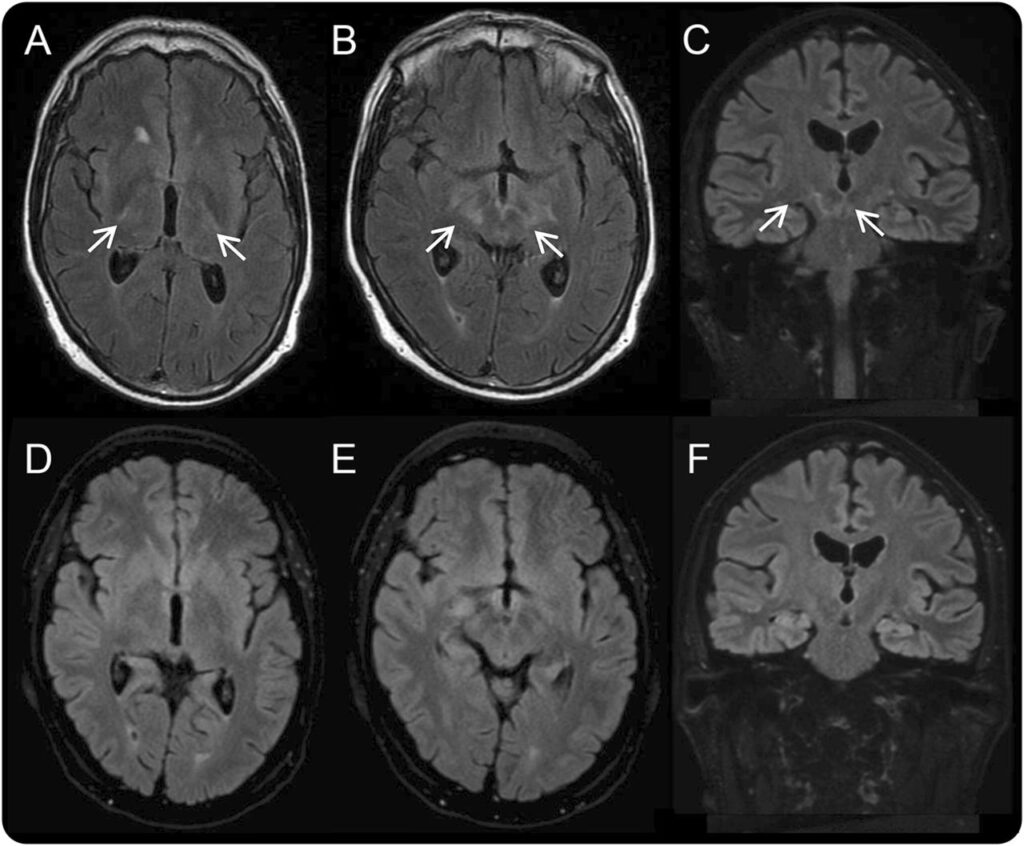

- Encephalitis (hjernebetændelse): En sjælden, men meget alvorlig komplikation, der kan føre til forvirring, personlighedsændringer, kramper og bevidsthedstab.

Ved mistanke om involvering af centralnervesystemet vil lægen ofte udføre en lumbalpunktur (rygmarvsprøve) for at analysere cerebrospinalvæsken. Her leder man efter tegn på inflammation samt specifikke antistoffer mod Borrelia, som produceres lokalt i nervesystemet. Fundet af disse antistoffer i rygmarvsvæsken er et stærkt bevis for neuroborreliose.